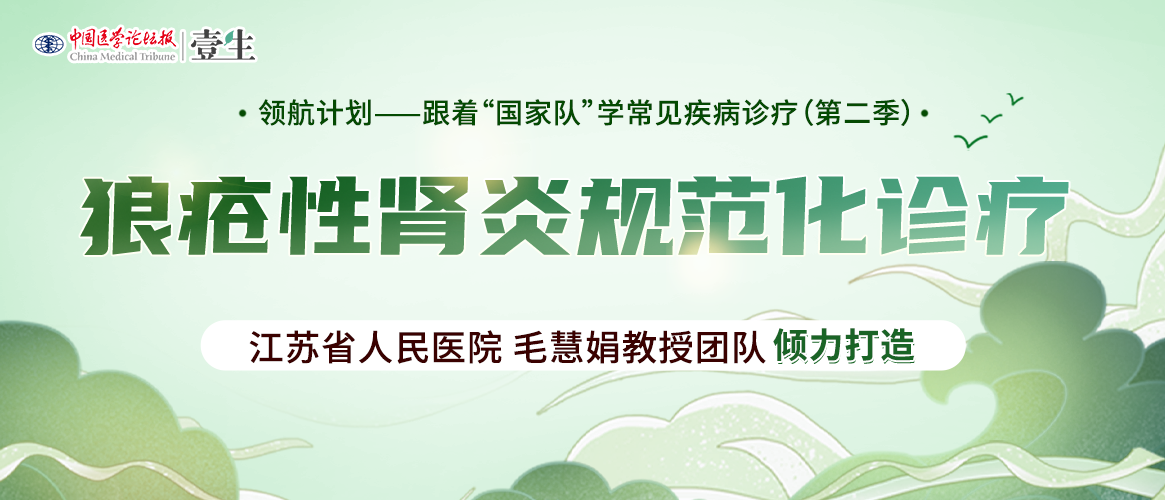

狼疮性肾炎I型(轻微病变性LN)小球基本正常(PASM染色)

狼疮性肾炎Ⅱ型(系膜增生性LN)小球系膜细胞、基质轻度增生,无内皮细胞增生及肾小球的硬化(PAS染色)